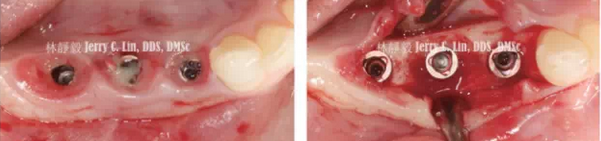

嚴(yán)重種植體周圍炎的處理(二)——林靜毅醫(yī)師